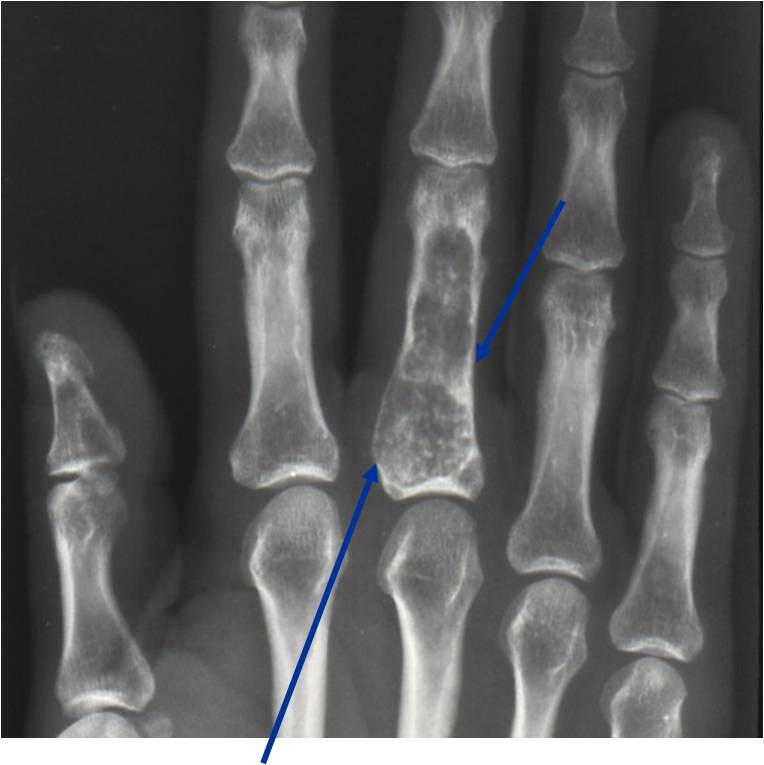

- Localized, radiolucent defect usually with punctate calcifications

- Calcifications are stippled, punctate, popcorn like calcifications and “Ring and Arc” calcifications

- Cartilage tumors grow in a lobular manner. The perimeters of the lobules undergo

- enchondral ossification that may calcify. If the entire perimeter of the lobule calcifies it appears

- radiographically as a “Ring”. If a portion of the perimeter of a lobule calcifies it forms an “Arc” on

- an X-ray.

- Cortex may be scalloped and thinned in the phalanges

- Geographic lytic lesion

- Expansile remodeling with thinned cortex

- Chondroid matrix with calcifications in majority of tumors